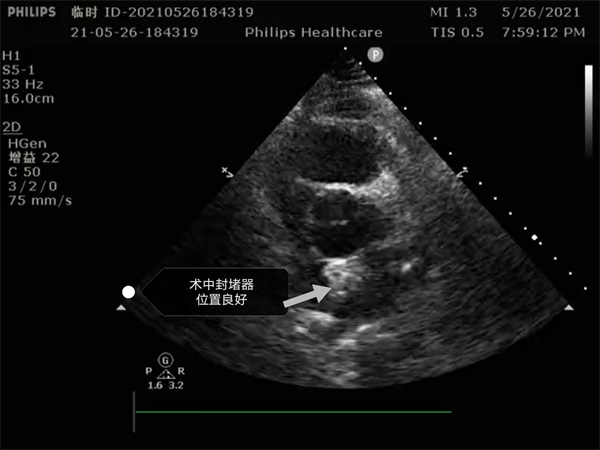

尤其是患者是個三房心,正常的人是有二個心房,這是一種少見的先天性心臟畸形, 如何在三房心把這個洞堵住,而且不影響心臟正常結(jié)構(gòu),是這個手術(shù)難點(diǎn)。沈主任組織全科進(jìn)行術(shù)前討論,5月26日下午5點(diǎn)開始手術(shù),導(dǎo)絲如何在不規(guī)則的只有米粒大小的卵圓孔里通過,鞘管如何通過,如何進(jìn)入卵圓孔連接的副房,避免封堵器夾住隔膜,這些難點(diǎn)在術(shù)中被沈主任團(tuán)隊(duì)一一化解,手術(shù)歷時二小時,隨著封堵器成功釋放,導(dǎo)管室外響起來熱烈的掌聲。